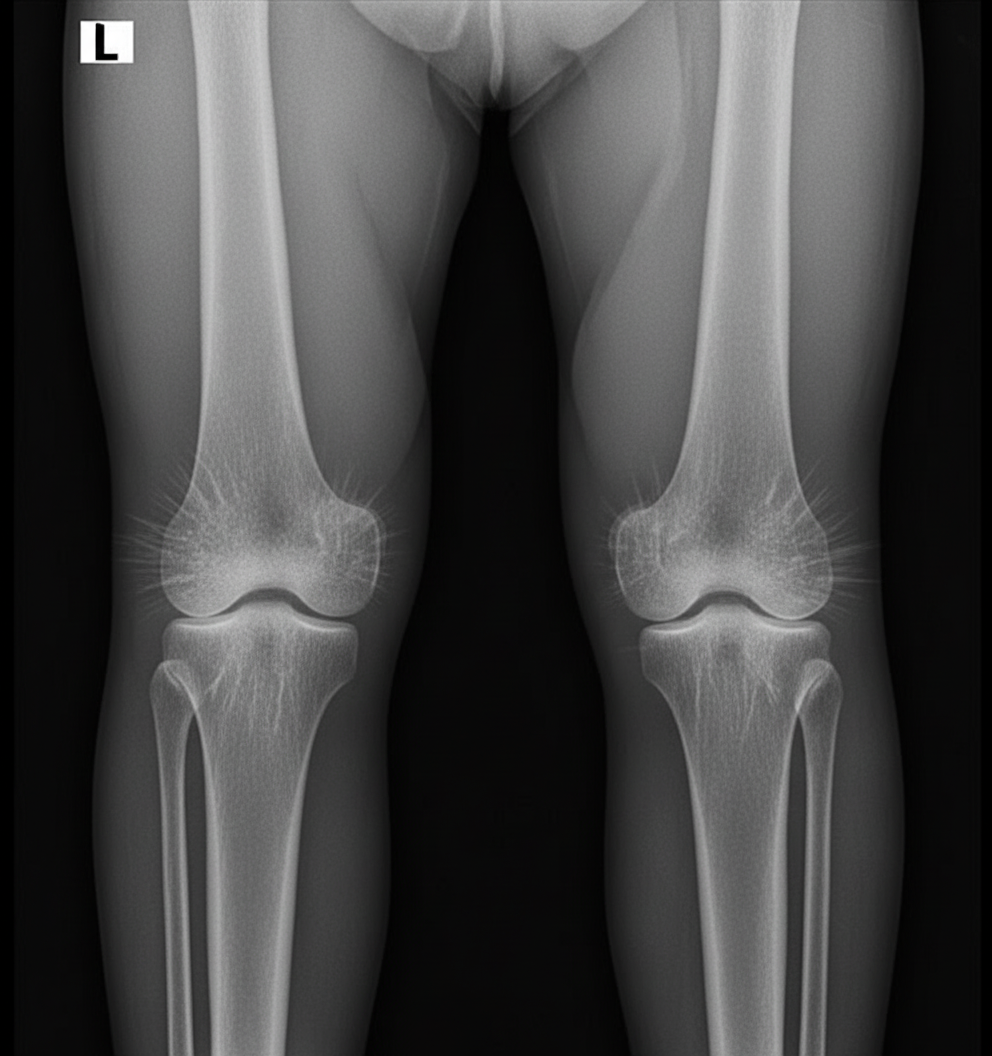

A 17-year-old boy presents to the clinic complaining of a painless lump on the lateral aspect of his left knee. The radiograph of the patient is shown below. Which of the following is the most likely diagnosis?

Explanation: ***Osteochondroma*** - The radiograph displays a classic **bony exostosis** with a stalk (pedunculated) arising from the metaphyseal region of the distal femur, which is the pathognomonic appearance of an osteochondroma. - These are the most common benign bone tumors, typically presenting in adolescents as a painless, slow-growing mass near the **growth plates** of long bones, especially around the knee. *Enchondroma* - An enchondroma is a benign cartilaginous tumor that develops *within* the **medullary cavity** of a bone, not as an external projection. - They are most commonly found in the small bones of the hands and feet and appear as a lytic lesion with characteristic **"rings and arcs" calcification** on radiographs. *Chondroblastoma* - This is a rare benign cartilaginous tumor that characteristically arises in the **epiphysis** of long bones in skeletally immature patients. - Radiographically, it appears as a well-defined, lytic lesion, often with a thin **sclerotic rim**, located in the end of the bone, unlike the metaphyseal outgrowth seen here. *Giant cell tumor* - This is a locally aggressive tumor that typically affects the **epiphysis** of long bones in skeletally mature adults (age 20-40). - It appears as an eccentric, lytic lesion with a **"soap bubble"** appearance that extends to the subchondral bone, which is inconsistent with the presented image.